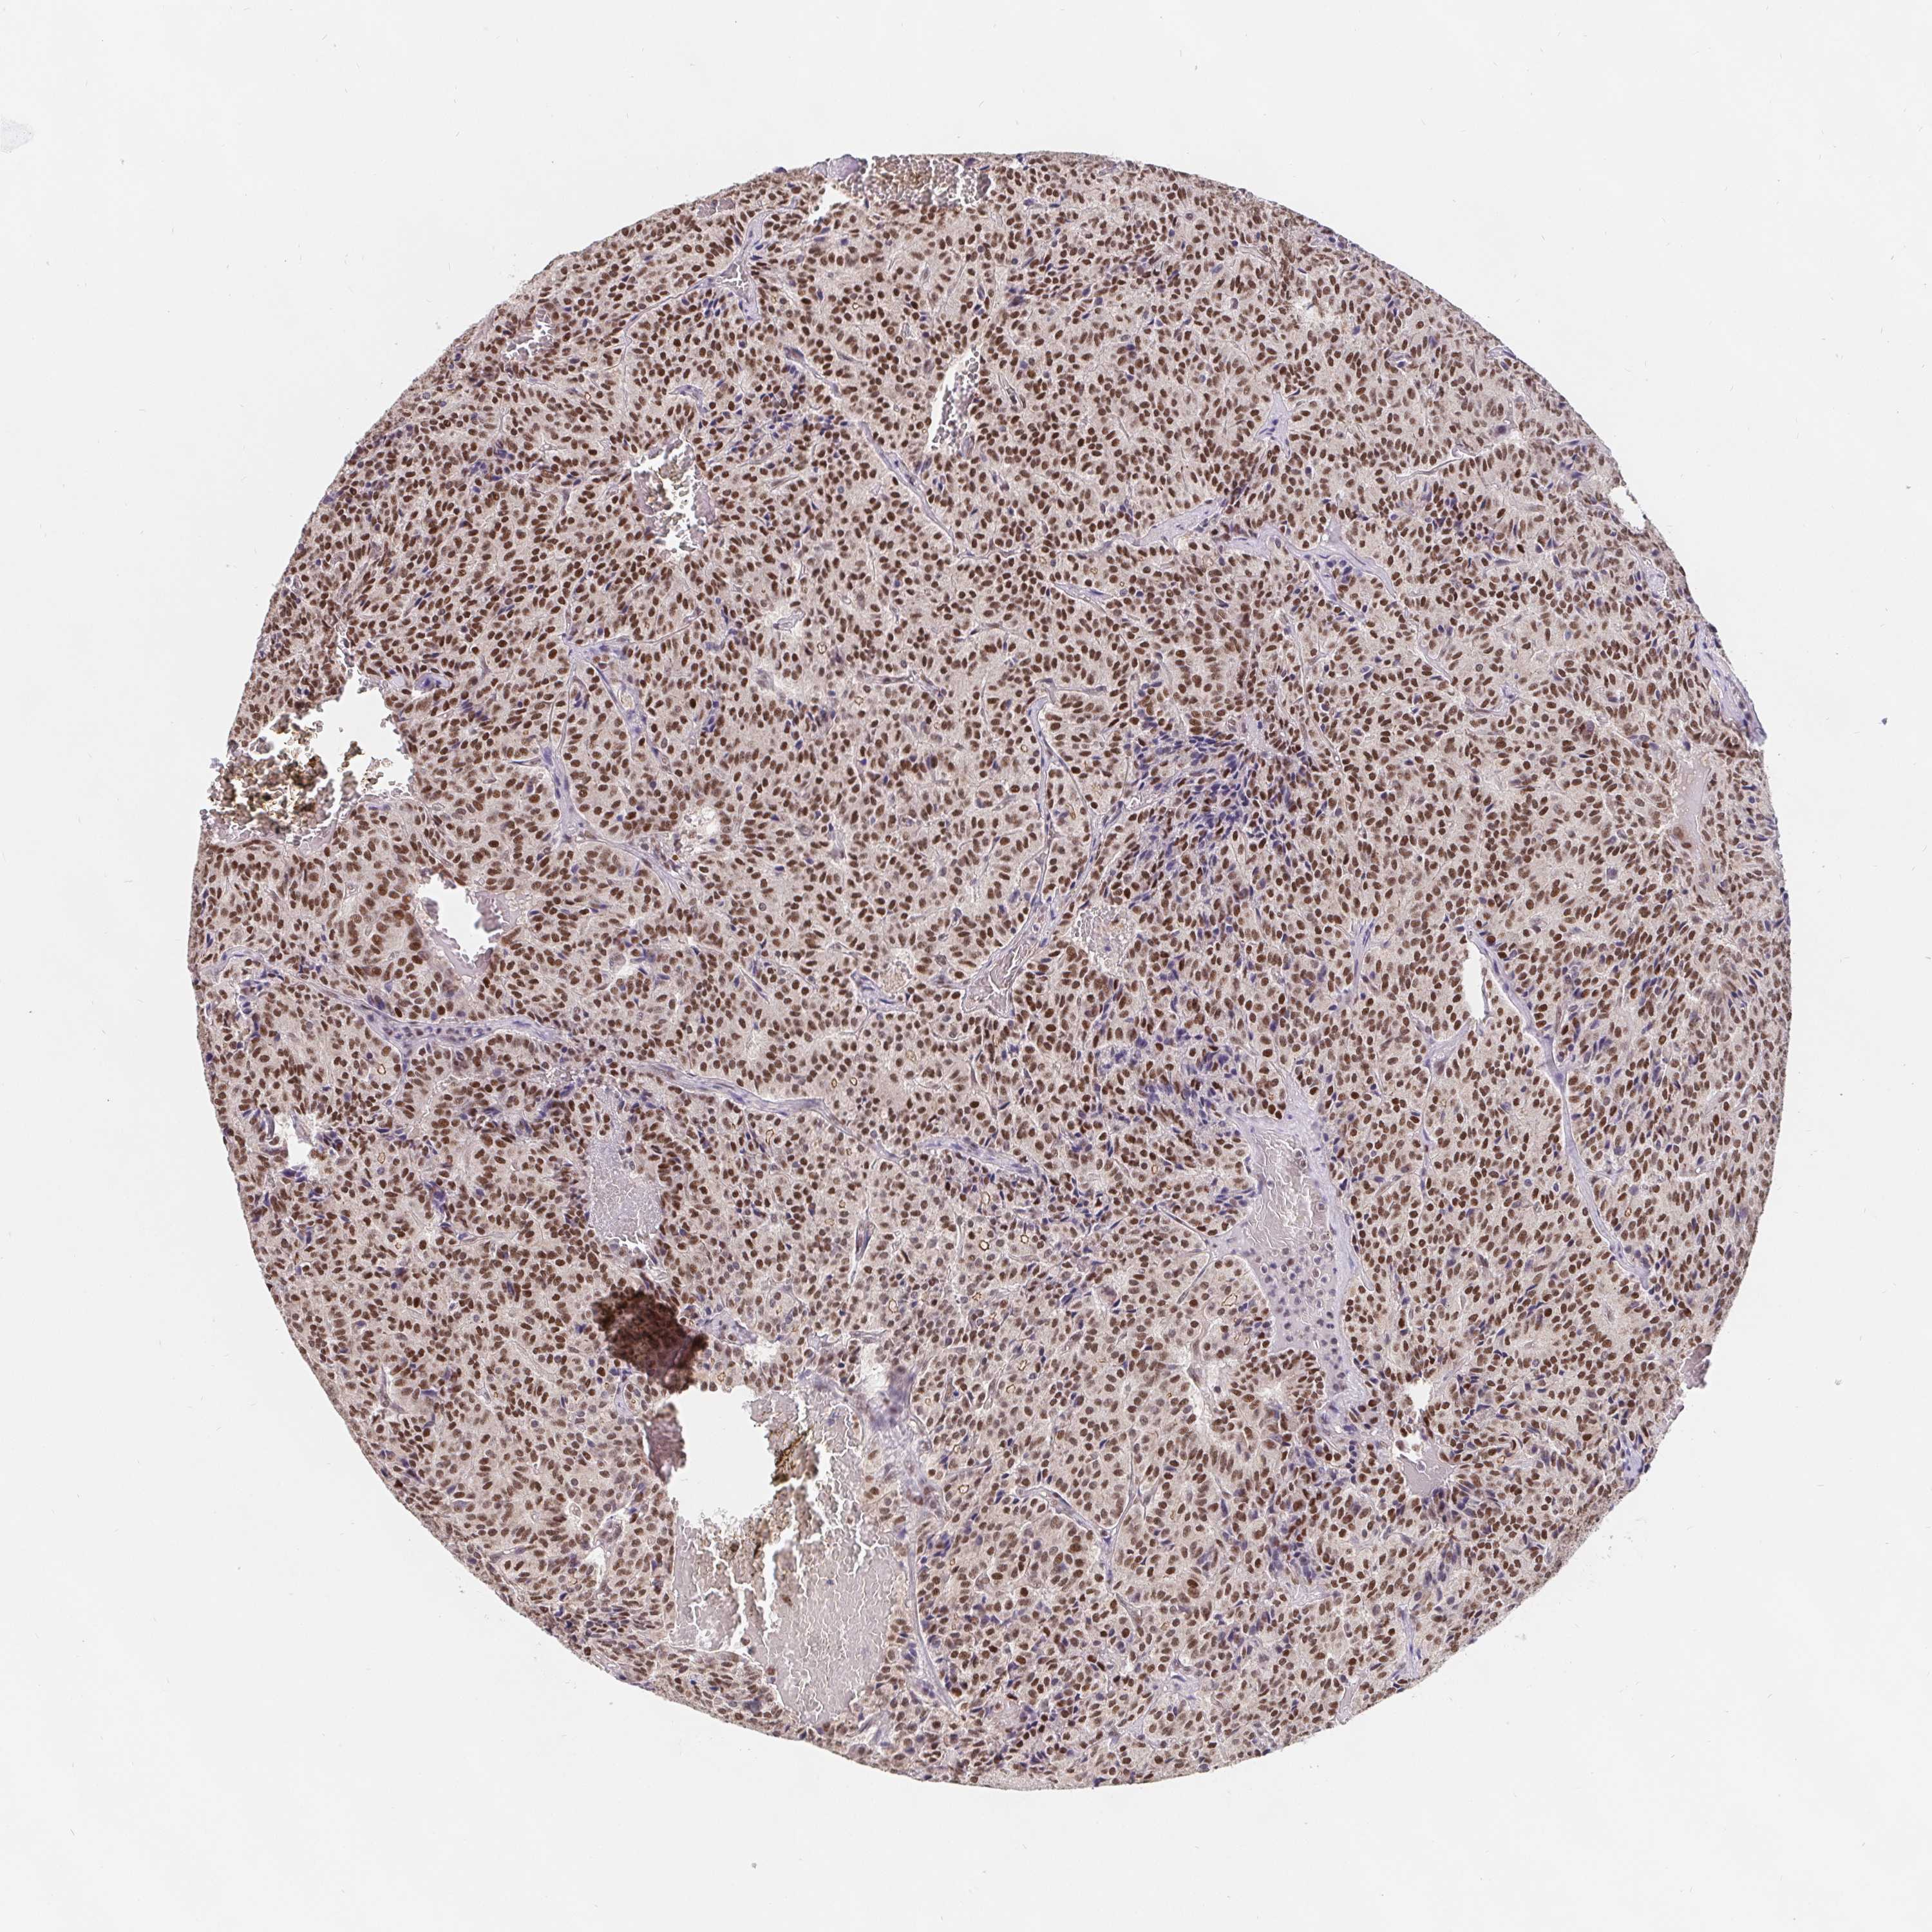

CARCINOID - Protein expressioni

A mouse-over function shows sample information and annotation data. Click on an image to view it in a full screen mode. Samples can be filtered based on level of antibody staining by selecting one or several of the following categories: high, medium, low and not detected. The assay and annotation is described here.

Antibody stainingi

Antibody staining in the annotated cell types in the current human tissue is reported as not detected, low, medium, or high, based on conventional immunohistochemistry profiling in selected tissues. This score is based on the combination of the staining intensity and fraction of stained cells.

Each image is clickable and will lead to virtual microscopy that enables deeper exploration of all samples and also displays staining intensity scores, fraction scores and subcellular localization as well as patient and tissue information for each sample.

Antibody HPA064323

Antibody CAB002608

Staining

High

Intensity

Quantity

Location

Carcinoid, malignant, NOS